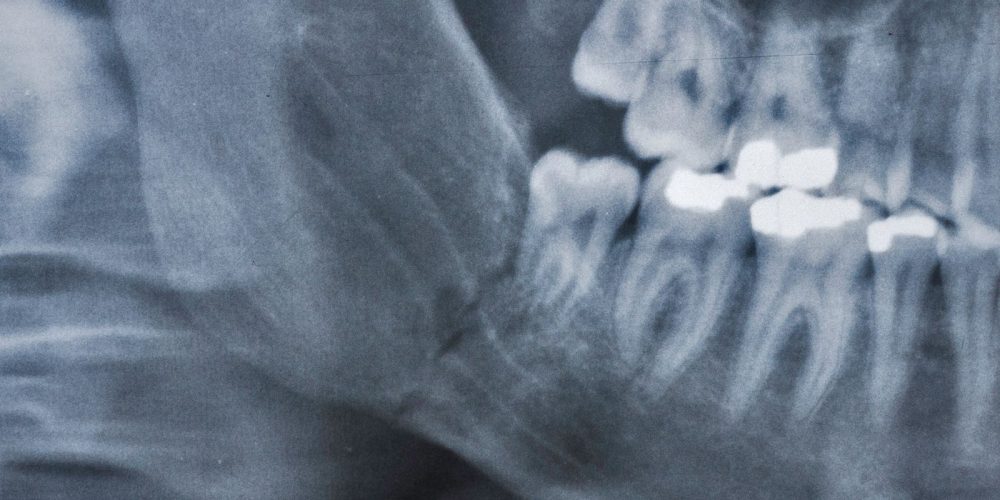

IMDO consiste en realizar mediante una pequeña intervención quirúrgica un corte al hueso entre el primer y segundo molar, para colocar un distractor mandibular. A partir del tercer día comenzamos a alargar la mandíbula activando el distractor a razón de 1 mm diario hasta llegar a la longitud deseada.